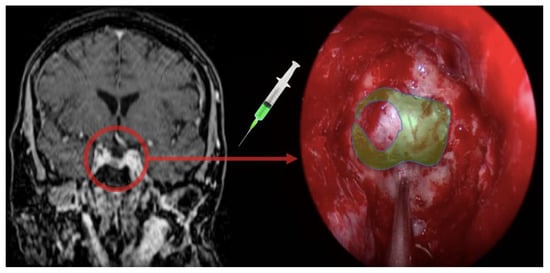

3.3. Fluorescein